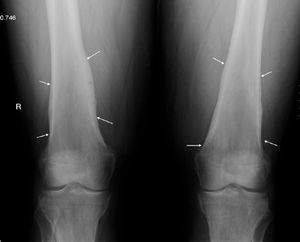

The patient, a 45-year-old male, was referred to the rheumatology clinic due to diffuse joint pain on the wrists and knees. The patient was diagnosed with liver cirrhosis and severe hepatopulmonary syndrome. Physical examination showed swelling of the knees and wrists (arthritis) and clubbing. The X-rays requested showed periosteal thickening observed continuously, in a diaphysometaphysiary location of the radius and ulna in both forearms, and predominantly in distal femurs and both knees, compatible with nonaggressive periosteal reaction. Fig. 1 shows periosteal thickening affecting both femurs on the concave bone edge and respecting the epiphysis, and equal involvement of the radius and ulna on the right wrist, in Fig. 2.

The findings on physical examination were finger-clubbing and arthritis of the hands and knees, and the radiological presence of continuous noninvasive periostitis of the concave edge affecting the long bones of both the upper and lower extremities, with a diagnosis of hypertrophic osteoarthropathy. This clinical entity is mainly associated with intrathoracic processes (especially malignancy, namely lung cancer and pleural tumors), but also other diseases among which one can include liver disease (hepatocellular carcinoma, alcoholic hepatitis and both Portal biliary cirrhosis and cirrhosis of the liver).1–3